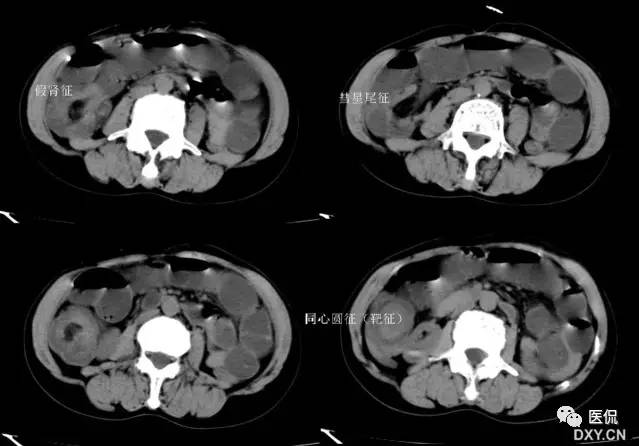

21 靶征(肠套叠)

是肠套叠最常见的特征性CT征像,为肠套叠长轴与CT扫描层面垂直时的表现,反映了套叠的各层肠壁、肠腔及肠系膜间的关系。典型排列为自外向内分别代表鞘部外层肠壁、鞘部肠腔内造影剂、鞘部内层肠壁、偏心性套入部肠系膜、套入部肠壁、套入部肠腔内造影剂。:

肠套叠是指一段肠管及与其相连的肠系膜(套入部)被套如其相连的一段长管内(鞘部),导致肠内容物通过阻碍。婴儿由于大肠与小肠管径之比例相差大。故小肠易陷入大肠而被套牢。少数肠套叠可能来自某些器质性病变如美凯尔憩室、肠息肉、异位胰腺小结、血管瘤、异物、复制肠管、淋巴增生、肿瘤、寄生虫等,其中以美凯尔憩室最多,过敏性紫斑也常会合并肠套叠,大于2岁的小孩发生肠套叠,一定要考虑到这些病变。大于5岁的病例中,则以淋巴瘤为最多;成人肠套叠小肠多见,常伴发良性病变;结肠型肠套叠则更多由恶性病变继发。良性病变有脂肪瘤、平滑肌瘤、血管瘤、神经纤维瘤、腺瘤样息肉、美克尔憩室、术后粘连机场动力性病变等;恶性病变有转移瘤、腺癌、类癌、淋巴瘤及平滑肌肉瘤等。由于肠套叠长轴与CT扫描层面的角度不同,表现各异。如扫描层面和迂曲的肠道相平行时,表现为彗星尾征或肾形征:即套叠近端肠系膜血管牵拉聚拢的征象。一般情况下,慧星尾征均与肾型肿块相伴出现。该肾形肿块为套鞘部游离缘与套入部近端肠管及肠系膜的CT斜切面图像,其中游离的套鞘呈弧形围绕套入部,形状若肾轮廓外形,而套入部近端肠管、肠系膜形状若肾蒂。此时,所谓慧星尾征的组成还应包括套入近端肠管。如果套叠的肠管与CT扫描垂直,则呈靶形征,即肿块影表现为圆形或类似环形。通常在肿块内可分辨出层样结构,推测可能是继发于套入部和鞘部间的液体或是肠壁水肿造成密度对比,类似同心圆形;当套入部肠壁显著水肿坏死或套入部肿瘤周围浸润累及肠系膜,肠系膜血管及脂肪、套叠时间较长,套入部系膜血管受挤压时,静脉血液回流障碍,套入部肠壁充血水肿、变硬,形成不完全性肠梗阻,套叠以上肠管蠕动增强,可引起代偿性肠管扩张肥厚,并可见肠系膜连同其血管纠集、扭曲,形成“漩涡征”。

成人肠套叠还有一些间接征象可帮助诊断,如肠壁不规则增厚或见密度不均匀的软组织块影,伴周围系膜及筋膜浸润、腹膜后淋巴结增大,则提示病因是恶性肿瘤。肿瘤所致肠壁水肿、坏死与部分炎症引起的套叠无法明确区分,肠壁及肠系膜血管有增厚伴肠壁内气体影的征象可提示血运障碍。如CT显示肠套叠直接征象、并伴随近段肠梗阻征象,则表示套入时间较长。如果套入部肠壁及鞘部组织发生水肿、变硬,形成不完全性肠梗阻,套叠以上肠管蠕动增强,可引起代偿性肠管扩张肥厚。

肠套叠形成的“靶征”

扫描层面和迂曲的肠道相平行时,表现为彗星尾征或肾形征:即套叠近端肠系膜血管牵拉聚拢的征象。